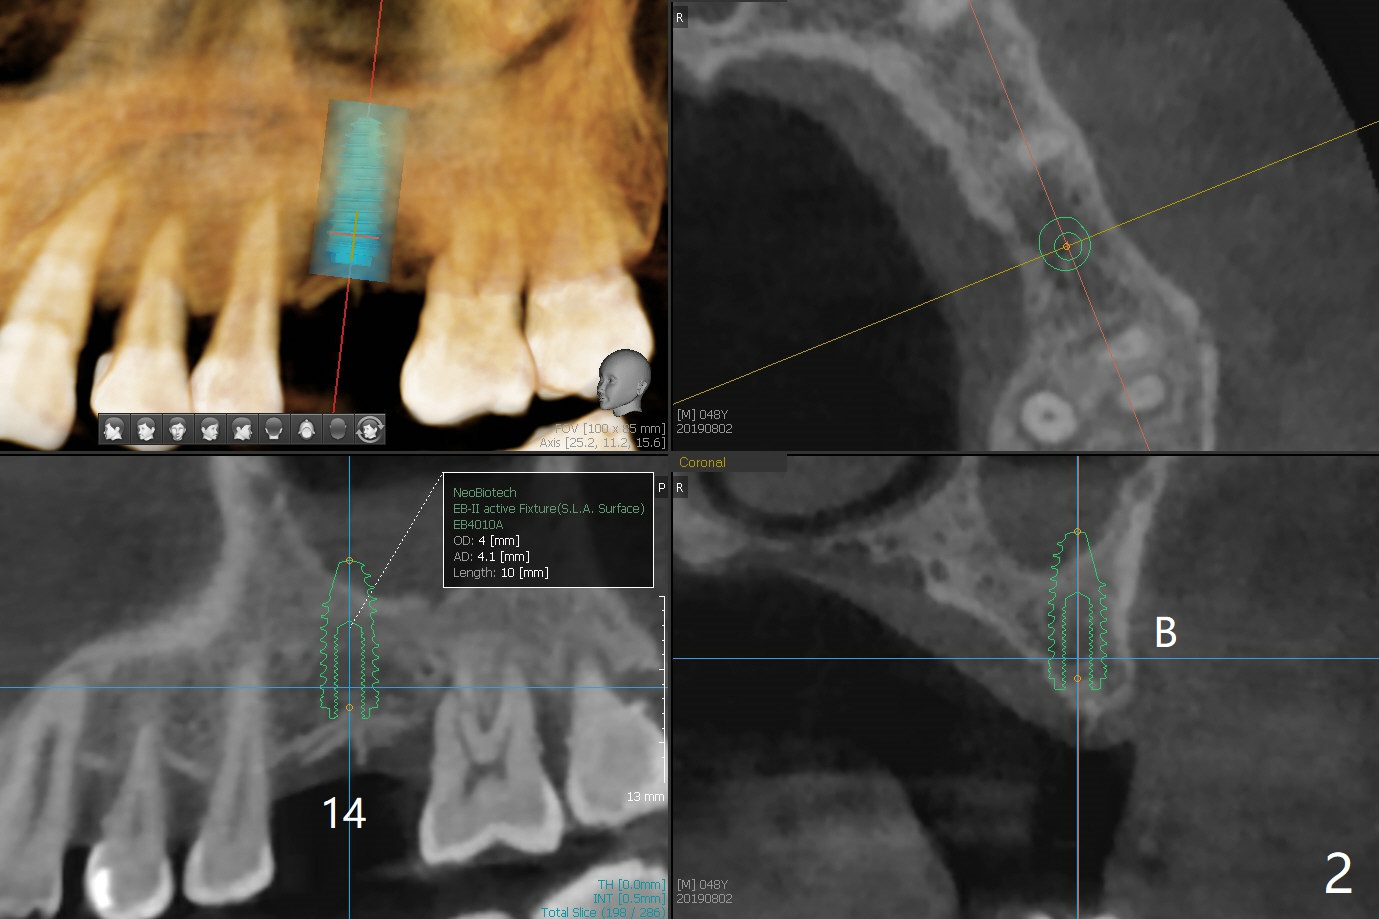

A 48-year-old man with chronic periodontitis wants an implant at #14 (Fig.1). The ridge is narrow. Bone expansion or underdrilling is required (Fig.2). PRF is prepared for sinus lift.